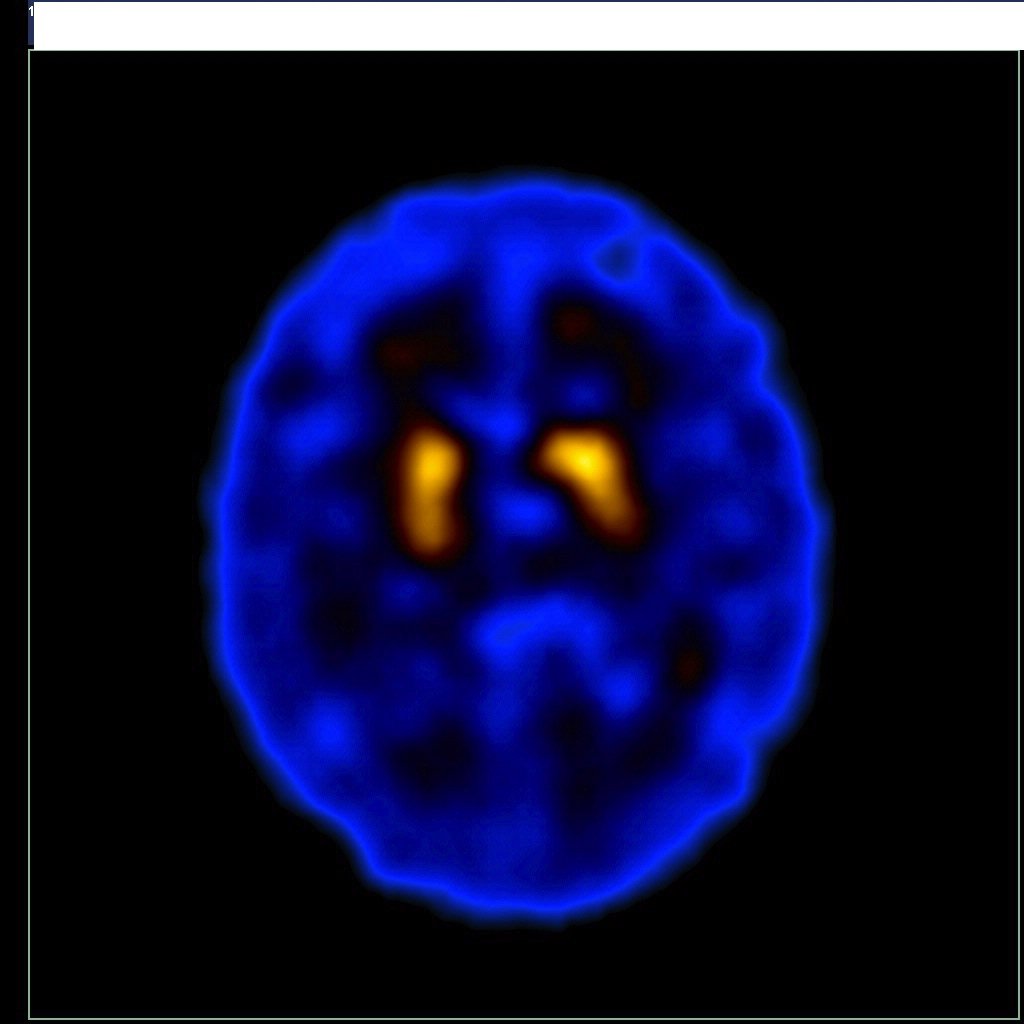

O exame é feito a partir da injeção intravenosa do Trodat (marcado com Tecnécio-99m), funcionando como uma espécie de “contraste”. A radiação emitida pelo radiofármaco é detectada pelo equipamento de cintilografia (gama-câmara), que fornece imagens tomográficas do cérebro, possibilitando que os médicos identifiquem as áreas afetadas e façam uma avaliação mais precisa do problema.